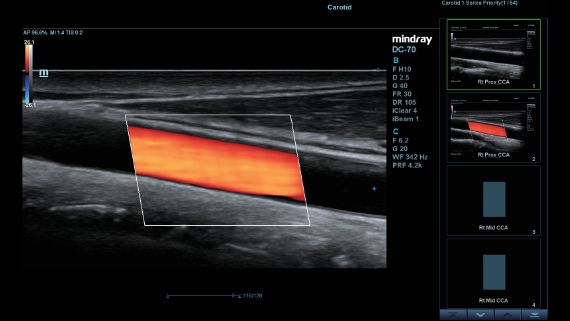

Klinische Bilder

Schallk?pfe